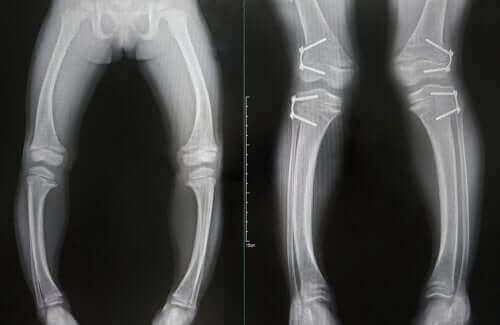

Charakteryzuje się opóźnieniem wzrostu, upośledzeniem odporności, łysieniem i ciężkimi deformacjami kości. Ten stan występuje najczęściej u dzieci w wieku od sześciu miesięcy do trzech lat, ponieważ jest to etap, w którym kości rosną najszybciej.

- Deformacje kości, które ulegają zmiękczeniu i wykrzywiają się na stałe podczas chodzenia. Może to spowodować u chorych trwałe wykrzywienie piszczeli. Ponadto, brak chrząstek może powodować ból i zużycie stawów już w młodym wieku.